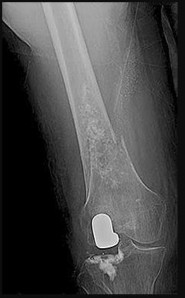

Question 9:

A 16-year-old male presents with a painful mass near his distal femur. Radiographs show a destructive, permeative lesion with a 'sunburst' periosteal reaction. Biopsy confirms osteosarcoma. Following standard neoadjuvant chemotherapy and wide surgical resection, which of the following is the most significant prognostic factor for long-term overall survival?

Correct Answer: Percentage of tumor necrosis in the resected specimen

Explanation:

In the treatment of high-grade osteosarcoma, the histologic response of the tumor to neoadjuvant chemotherapy (measured by the percentage of tumor necrosis in the definitive surgical specimen) is widely considered the single most important prognostic factor for long-term survival. A good response is typically defined as >90% or >95% necrosis. Limb salvage versus amputation does not impact overall survival, provided negative surgical margins are obtained.